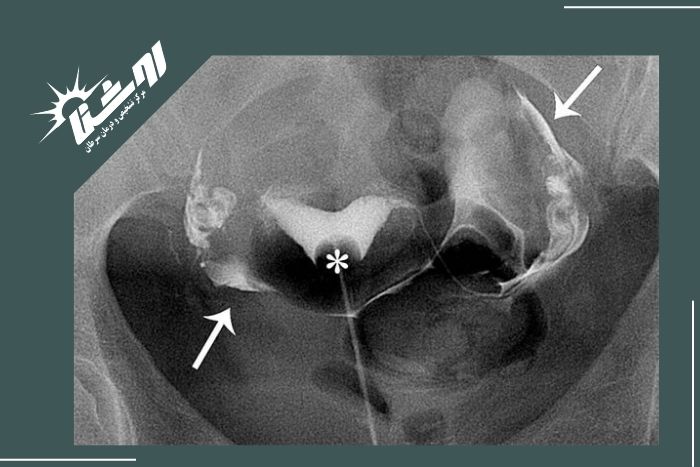

بهترین زمان برای انجام عکس رنگی رحم معمولاً بین روزهای هفتم تا دهم سیکل قاعدگی است. در این بازه رحم از خونریزی پاک شده و احتمال بارداری وجود ندارد بنابراین نتیجه دقیقتر خواهد بود. البته زمان دقیق انجام این بررسی را پزشک شما مشخص میکند چون ممکن است بر اساس شرایط بدنی و نوع سیکل قاعدگی زمان مناسب کمی متفاوت باشد.مشاوره با پزشک